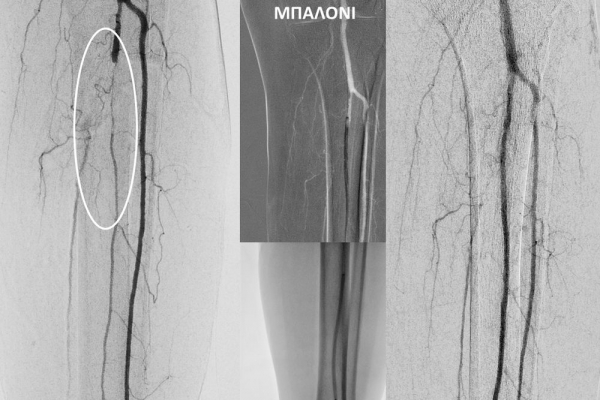

O σακχαρώδης διαβήτης είναι μεταβολική ασθένεια η οποία χαρακτηρίζεται από αύξηση της συγκέντρωσης του σακχάρου στο αίμα (υπεργλυκαιμία) και διαταραχή του μεταβολισμού της γλυκόζης. Ο βαθμός αύξησης της γλυκόζης στο αίμα και η παραμονή των αυξημένων τιμών της για μεγάλο χρονικό διάστημα βλάπτουν, κυρίως, τα μικρά αγγεία, προκαλώντας διαβητική νευροπάθεια, διαβητική νεφροπάθεια, αμφιβληστροειδοπάθεια κ.τ.λ., με σοβαρότατες συνέπειες σε πολλά όργανα-συστήματα.Στην Ελλάδα κάθε χρόνο πραγματοποιούνται 2.000 – 3.000 ακρωτηριασμοί κάτω άκρων, αφού το 4-5% των πασχόντων από διαβήτη εμφανίζει περιφερική αγγειοπάθεια με έλκη ή και γάγγραινα στα πόδια. Σε ποσοστό 80% οι ακρωτηριασμοί θα μπορούσαν να αποφευχθούν και η επεμβατική ακτινολογία μπορεί να βοηθήσει σημαντικά.Η διαδερμική ενδαγγειακή αγγειοπλαστική (percutaneous transluminal angioplasty, PTA) είναι μια ελάχιστα επεμβατική μέθοδος αντιμετώπισης των αρτηριακών στενώσεων ή και αποφράξεων του διαβητικού ποδιού (περιφερικήδιαβητικήαρτηριοπάθεια).